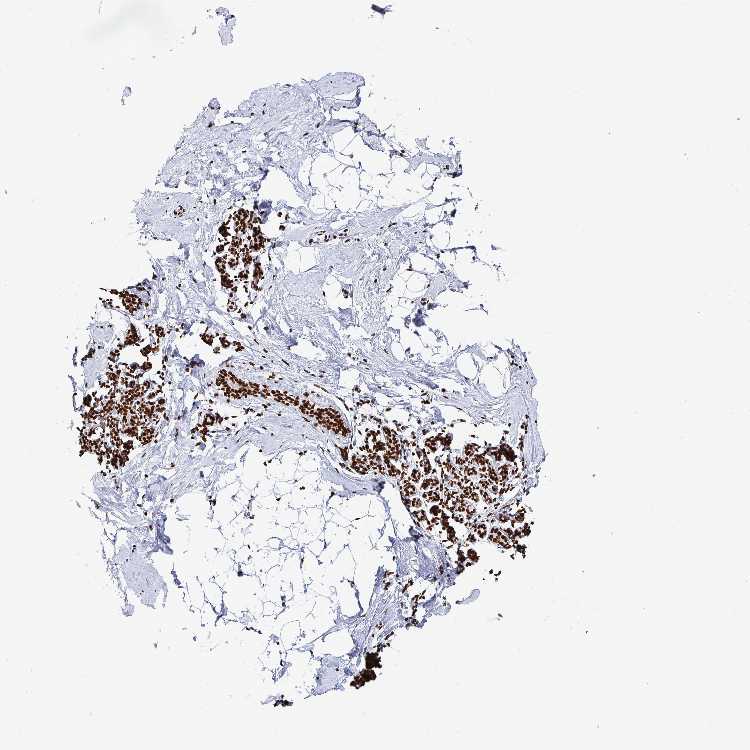

BREAST - Antibody stainingi

Antibody staining in the annotated cell types in the current human tissue is reported as not detected, low, medium, or high, based on conventional immunohistochemistry profiling in selected tissues. This score is based on the combination of the staining intensity and fraction of stained cells.

Each image is clickable and will lead to virtual microscopy that enables deeper exploration of all samples and also displays staining intensity scores, fraction scores and subcellular localization as well as patient and tissue information for each sample.

Antibody HPA059098

Adipocytes High

Glandular cells High

Myoepithelial cells High